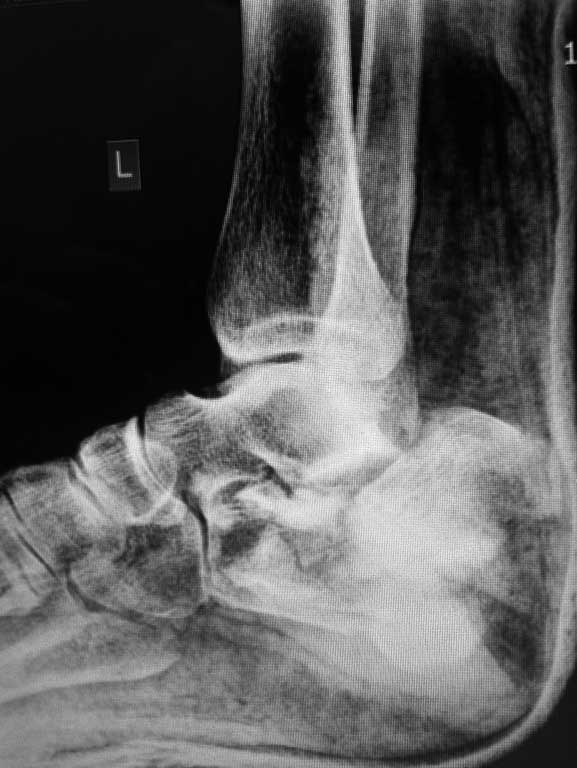

Уважаемые коллеги!Представляю вашему вниманию следующий случай, интересуют ваши

предложения по выбору метода оперативного лечения перелома пяточной кости.

Больной Н., 38 лет, к нам переведен из другого ЛПУ, травма менее недели назад, в результате

ДТП, получил закрытый многооскольчатый перелом пяточной кости со смещением, так же есть на

этой же конечности перелом шейки бедра(базальный). Интересует ваше мнение по поводу выбора

оперативного метода?склоняемся к аппарату...